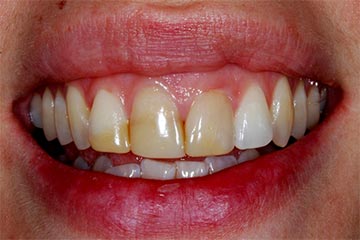

Con protesi fissa superiore e protesi fissa inferiore

sono stati sostituiti da 10 impianti, cioè protesi radicolari endo-ossee che sostengono le protesi fisse superiore ed inferiore.